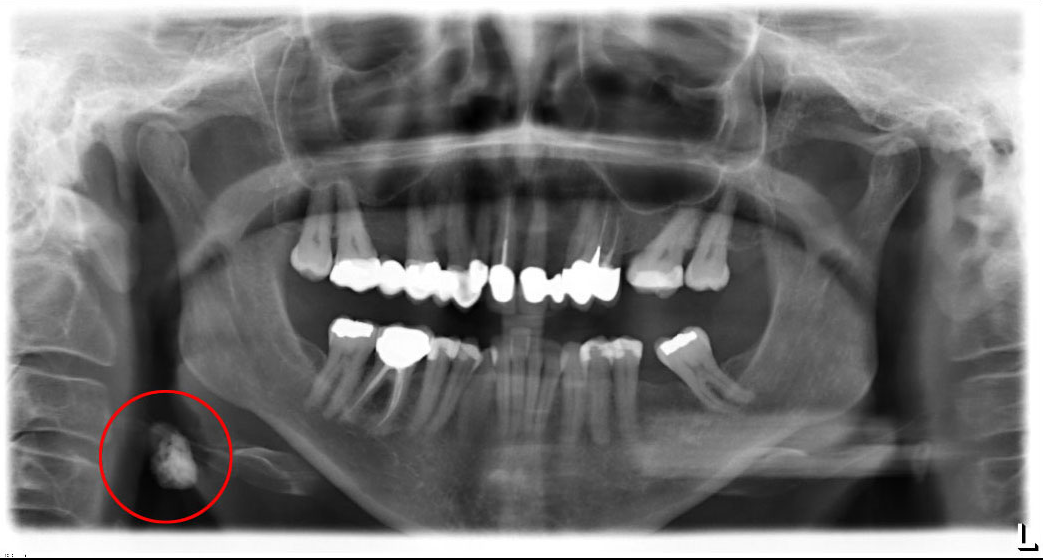

9. What condition can be seen in the following X ray? (the circle)